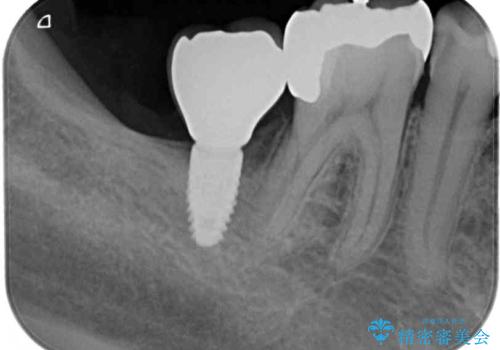

- 下顎左右の奥歯を治療途中で放置してしまっているとのことで来院された患者様です。

欠損部はインプラントによる補綴治療を、土台の外れてしまった歯は、根管治療を行った上で、補綴治療を行うこととしました。